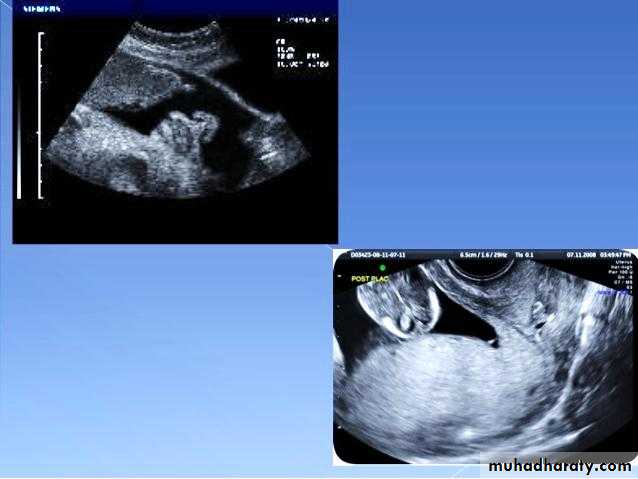

BPD together with head circumference (HC), abdominal circumference (AC), and femur length (FL) are computed to produce an estimate of fetal weight. In the second trimester this may be extrapolated to an estimate of gestational age and an estimated due date (EDD) .

The BPD should be measured on an axial plane that traverses the thalami, and cavum septum pellucidum. The transducer must be perpendicular to the central axis of the head, and thus the hemispheres and calvaria should appear symmetric.